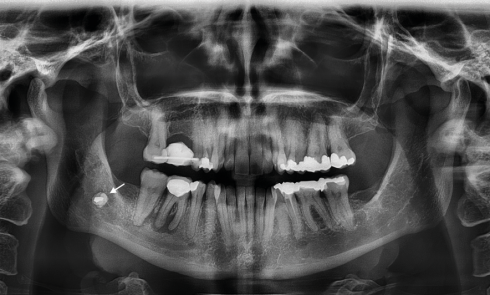

Imager la douleur orofaciale

Causes centrales et périphériques des douleurs orofaciales et implications dans le choix du bon examen d’imagerie Lors de l’anamnèse du patient...